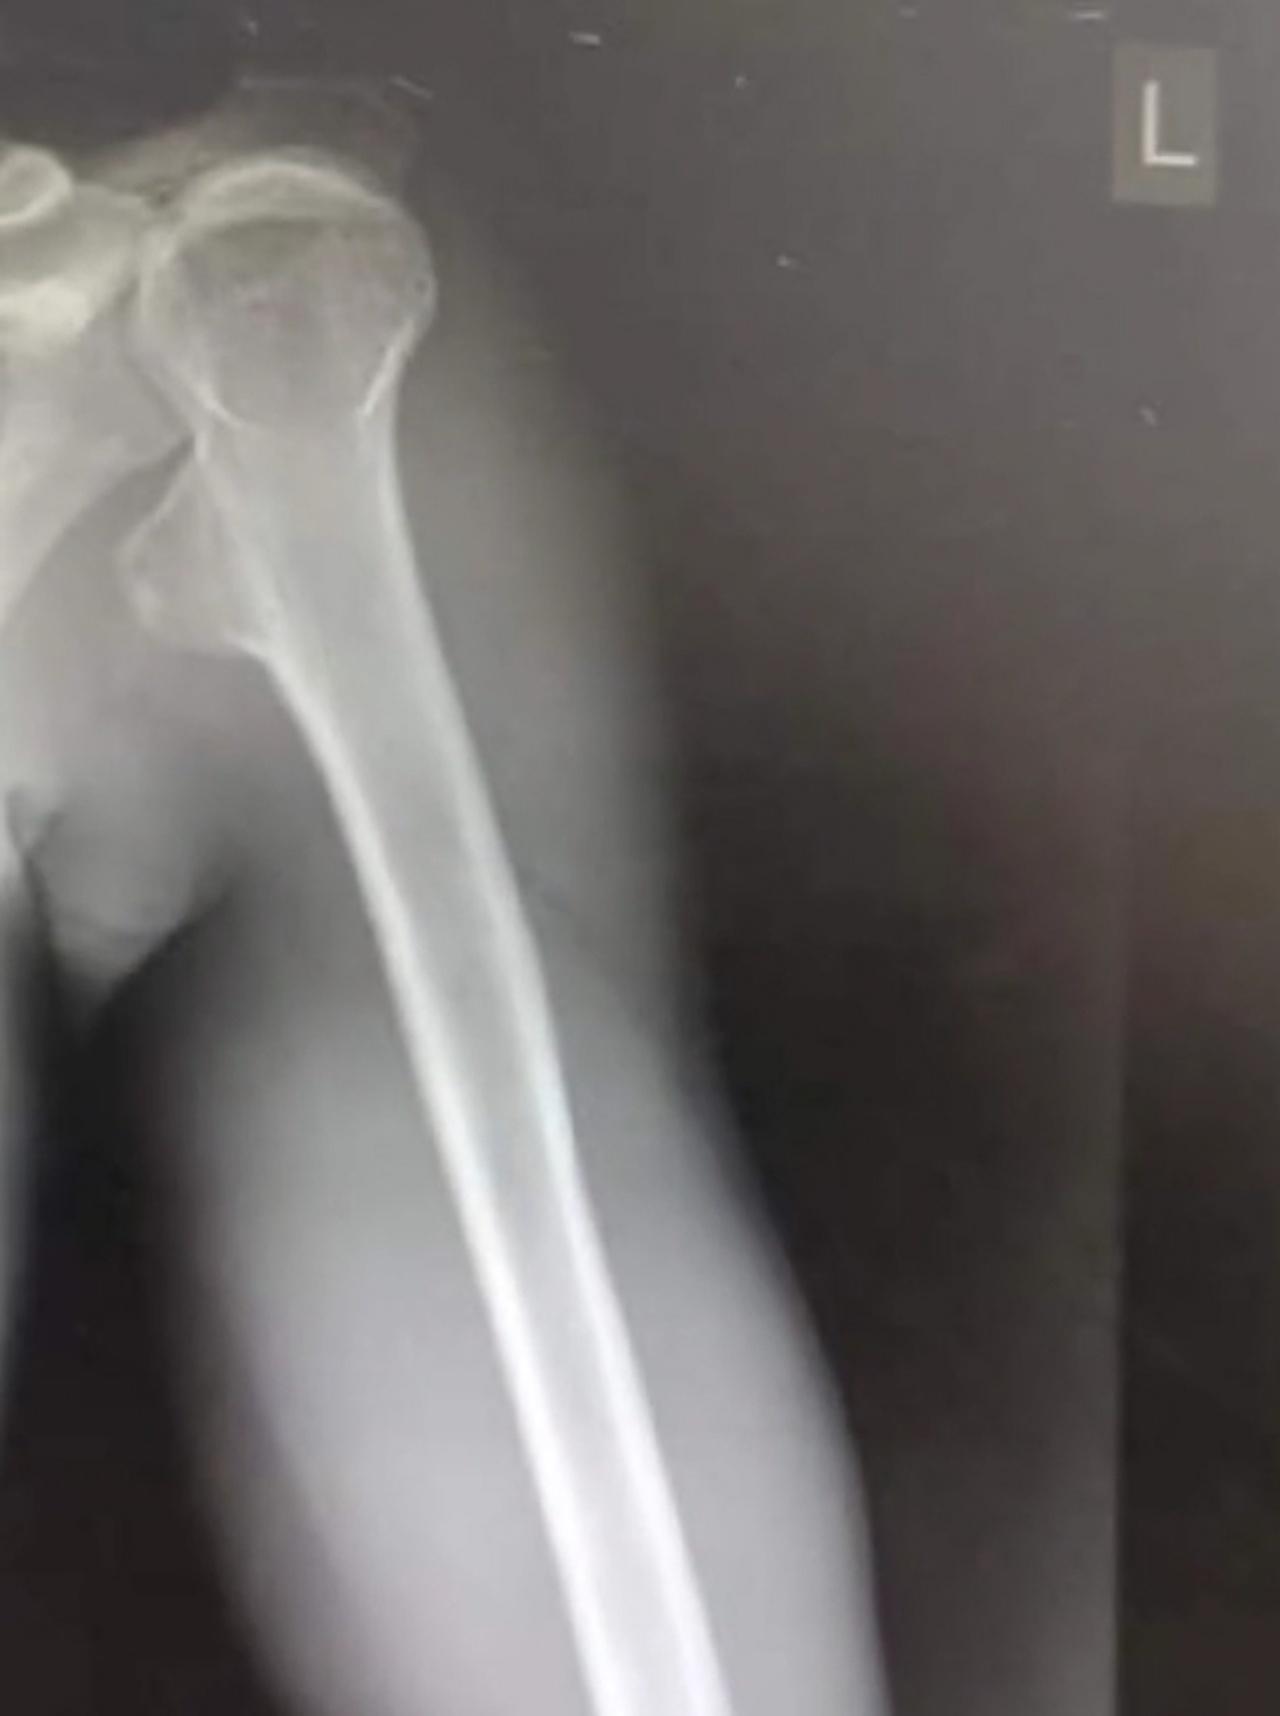

สำหรับชีวิตผมข้างต้น ได้แค่นี้ผมก็พอใจอย่างมากแล้วครับ และโรคมะเร็งที่ผมเป็น คือ มะเร็งกระดูก ที่มีเนื้องอกขนาด 4 ซม. ที่กระดูกแขน ปัจจุบันหายเป็นปกติแล้ว แต่ยังต้องตรวจระวังทุกๆ ปี

ต่อมา คุณสุวัฒน์ เพชรมาศศรี อายุ 25 ปี หนุ่มเจ้าของคลิปได้เปิดเผยกับ "ไทยรัฐออนไลน์" ว่า ตอนอายุ 17 มีก้อนเนื้อที่แขน ไปหาหมอบอกแค่เป็นกล้ามเนื้ออักเสบ ให้ยามากินก็ไม่หาย แต่ไม่มีอาการเจ็บปวด แม้ก้อนจะโตพอสมควร

เมื่ออายุประมาณ 19-20 ปี ได้มาทำงานรับจ้างแบกไม้กับน้า พร้อมกับรับจ้างแบกปาล์ม และกรีดยาง ทำงานโดยใช้ชีวิตได้ปกติทุกอย่าง แต่พอไปฝึกทหารเกณฑ์ ได้ไปตรวจดูก้อนเนื้ออีกครั้ง พบเนื้องอกที่กระดูกแขน ซึ่งเป็นร้ายของมะเร็งกระดูก ชนิดคอนโดรซาร์โคมา

จากนั้นได้รักษาที่โรงพยาบาลสงขลานครินทร์ คุณหมอผ่าตัดเนื้อร้ายออกได้หมด เพราะไม่ได้ลุกลามรุนแรง แต่ต้องติดตามอาการทุกๆ 6-12 เดือนเพื่อเฝ้าระวัง  ถามว่ามั่นใจว่าจะหาย 100% ไหม ก็ไม่มั่นใจขนาดนั้น แต่ทุกวันนี้ยังใช้ชีวิตปกติ สุขภาพแข็งแรงดี แต่สิ่งหนึ่งที่ไม่เคยเกิดกับตนเองเลย คือ ไม่มีอาการเจ็บปวดทรมาน หลังจากผ่าตัดเสร็จ ก็กลับไปทำงานเป็นกรรมกรเช่นเดิม เพื่อหาเงินเลี้ยงครอบครัว และใช้ในการรักษา